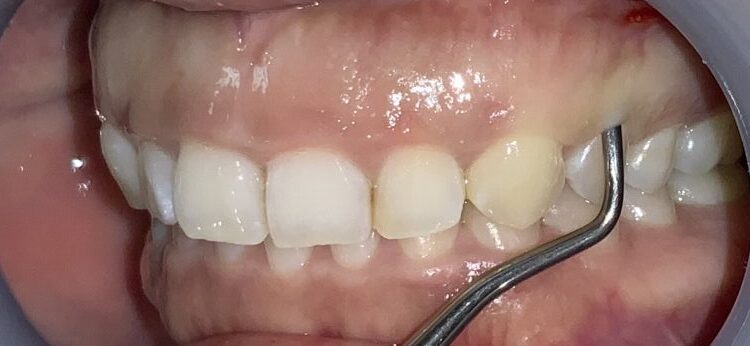

今回の患者様の治療前の状態です。

歯ぐきの長さに比較して、歯が少し小さいですね。歯ぐき自体は健康で綺麗なピンク色をしています。

一番気になる、前歯の歯と歯ぐきの位置状態の検査します。

こんなに歯ぐきがかぶさっています。

反対側の歯も調べてみます。前歯の形はとても大切ですから、慎重に検査を進めます。

この歯も同じように、たくさんの歯ぐきが、かぶさっています。